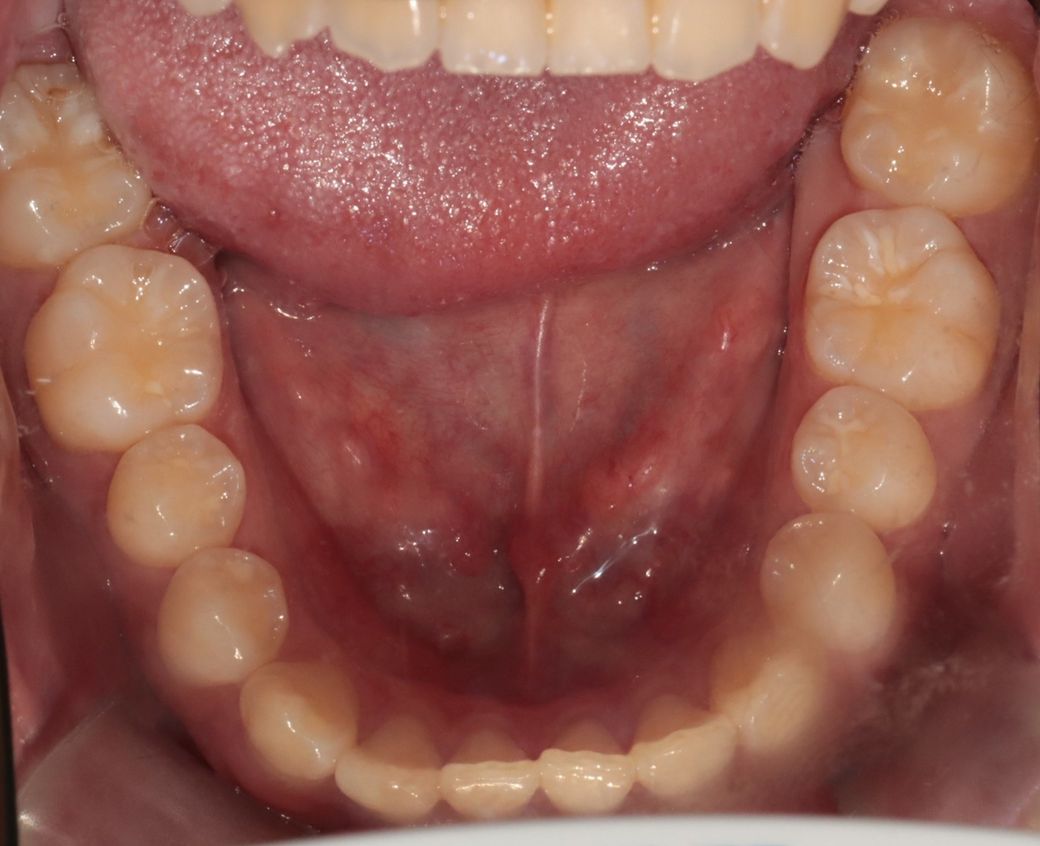

• 2번 째 사진

세가지 치과 모두 맞는 말입니다. 지금 보여주신 자료를 종합해보면 경미한 3급 부정교합입니다.

이 상태에서 교정도 가능하고 양악도 가능하지만 치료 이후 변화되는 모습에는 한계가 있습니다. 또한 부정교합 및 골격부조화가 심하지 않으므로 심미적으로 불편감이 없다면 3번 치과처럼 치료하지 않아도 됩니다. 물론 심미적으로 문제가 된다고 생각한다면 이때는 두가지 방법 모두 가능합니다.